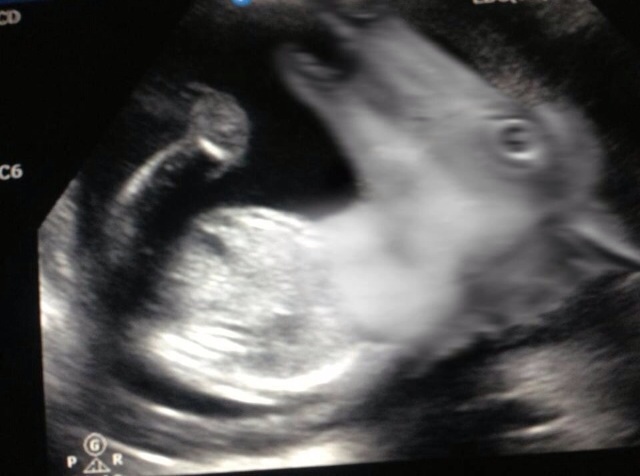

Mommy to Be!!!!!! :) :) :) :)